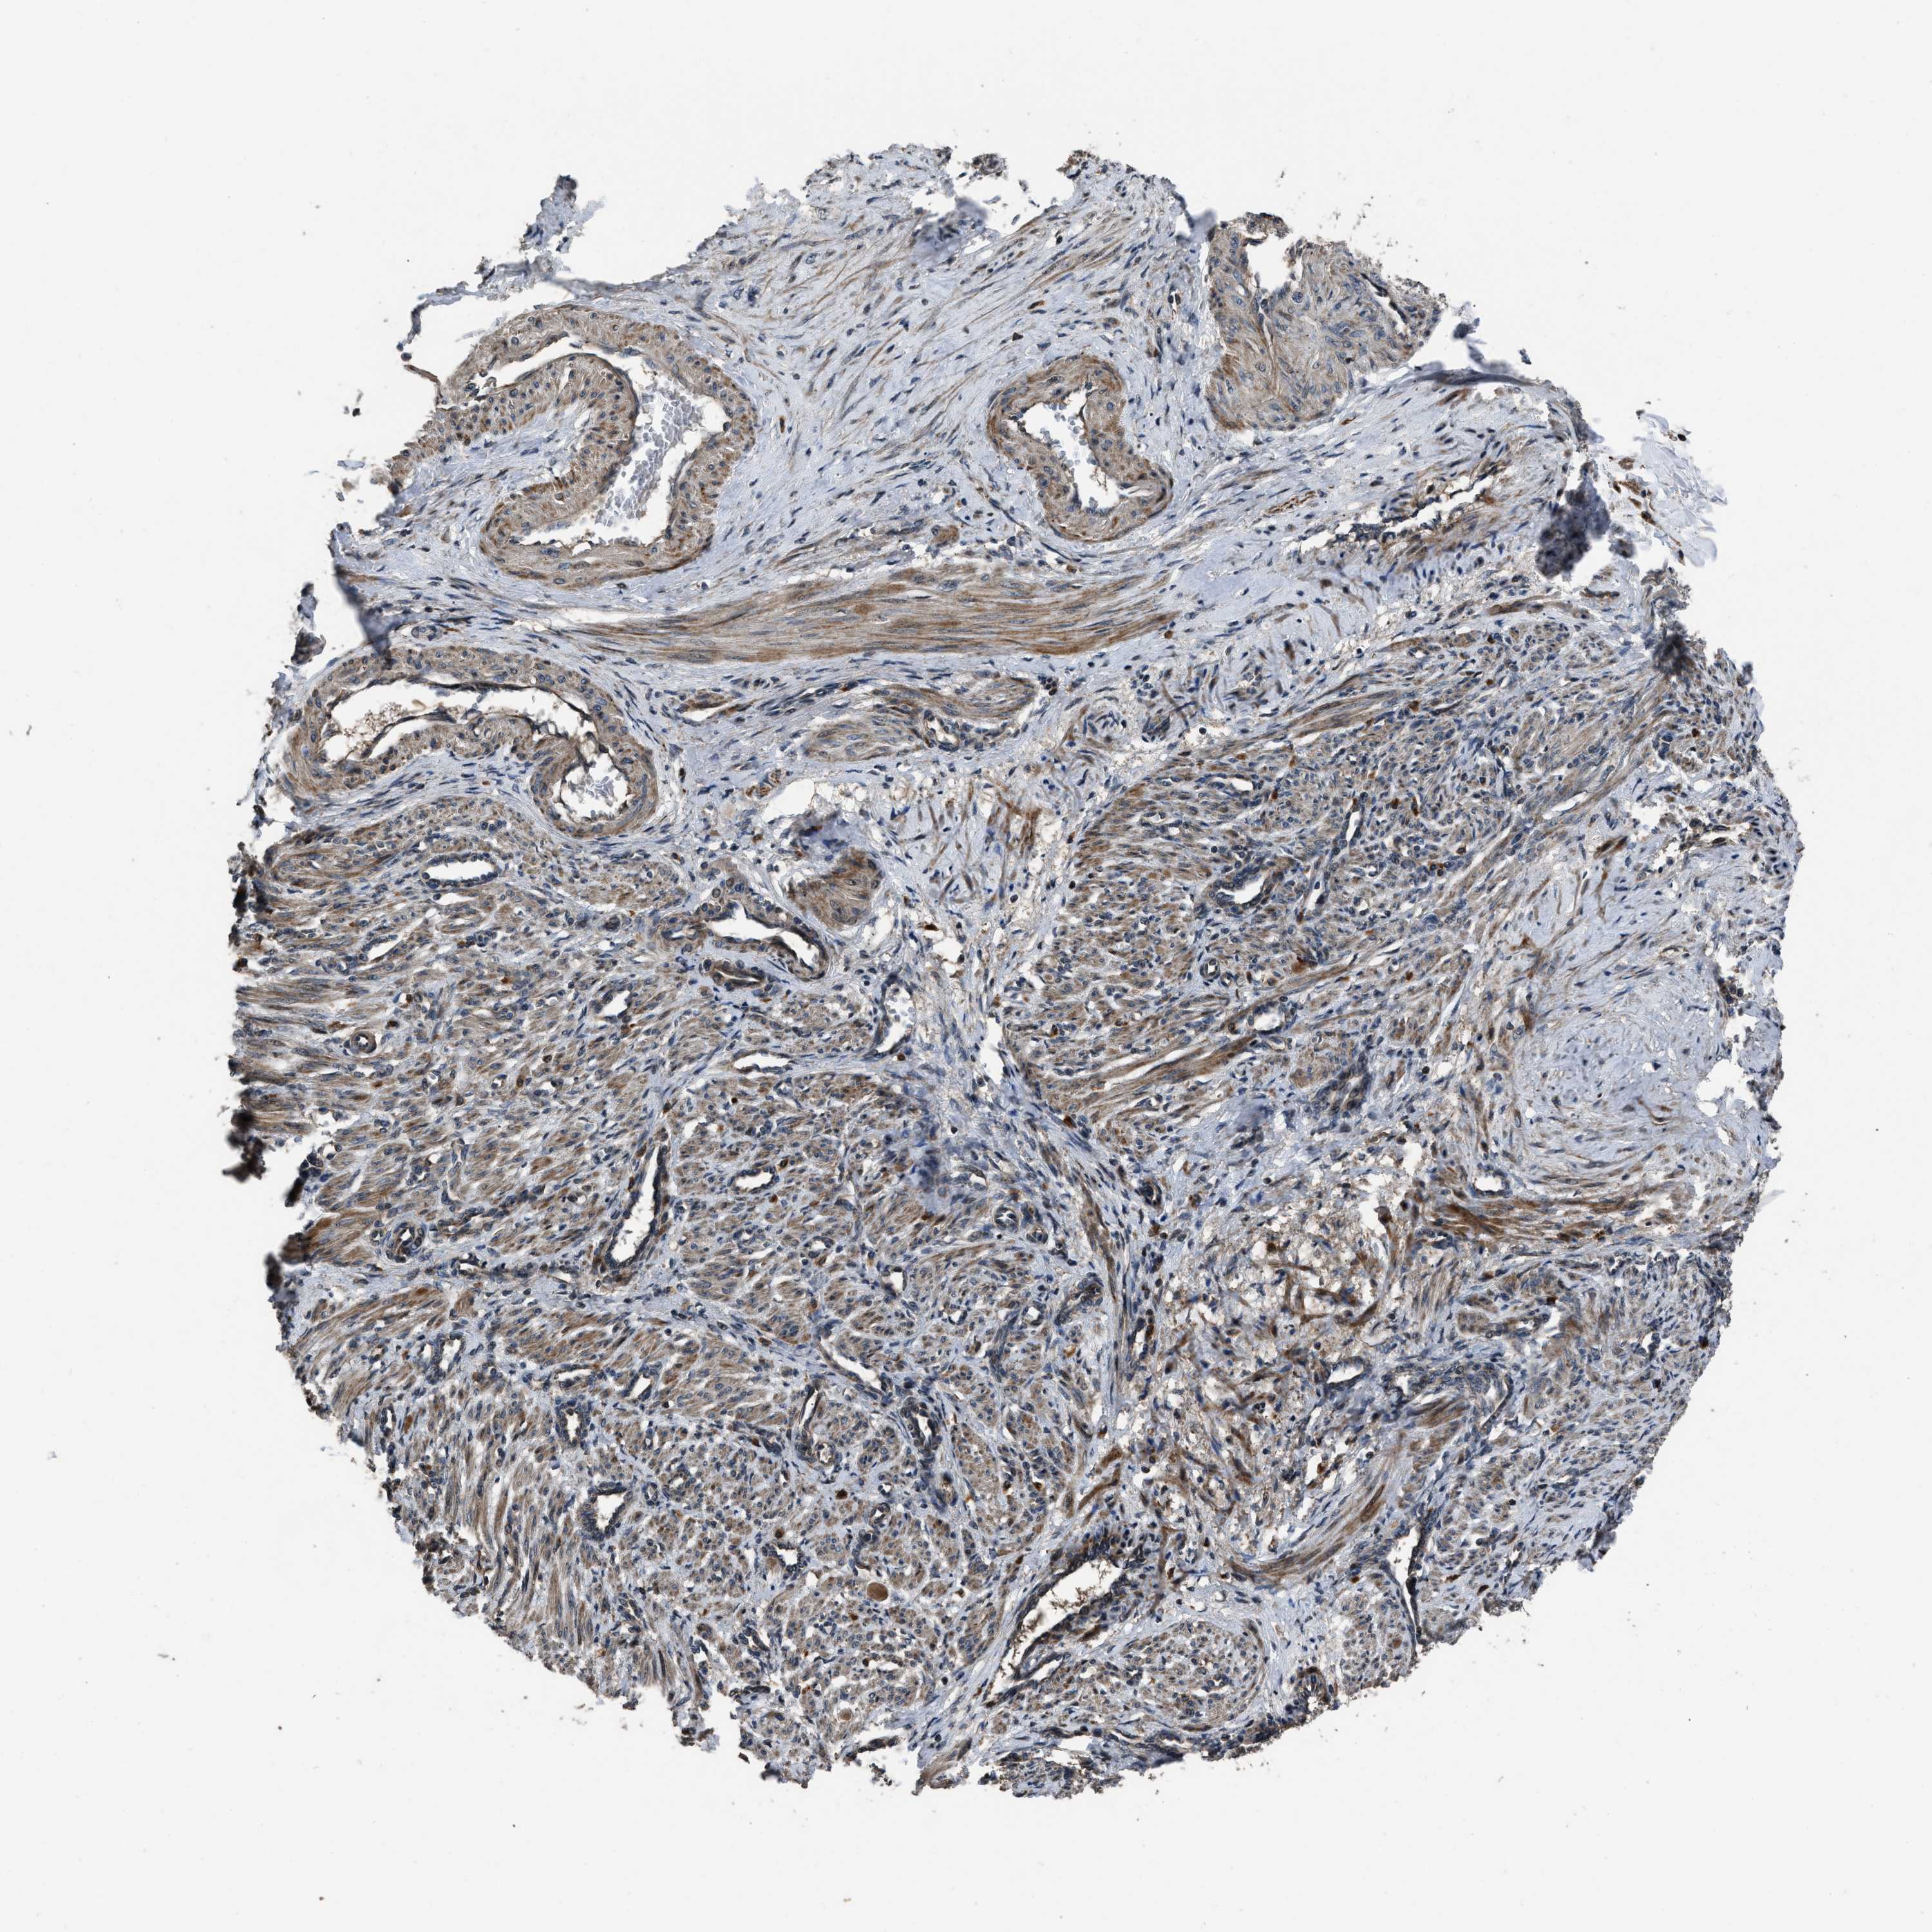

NSD3